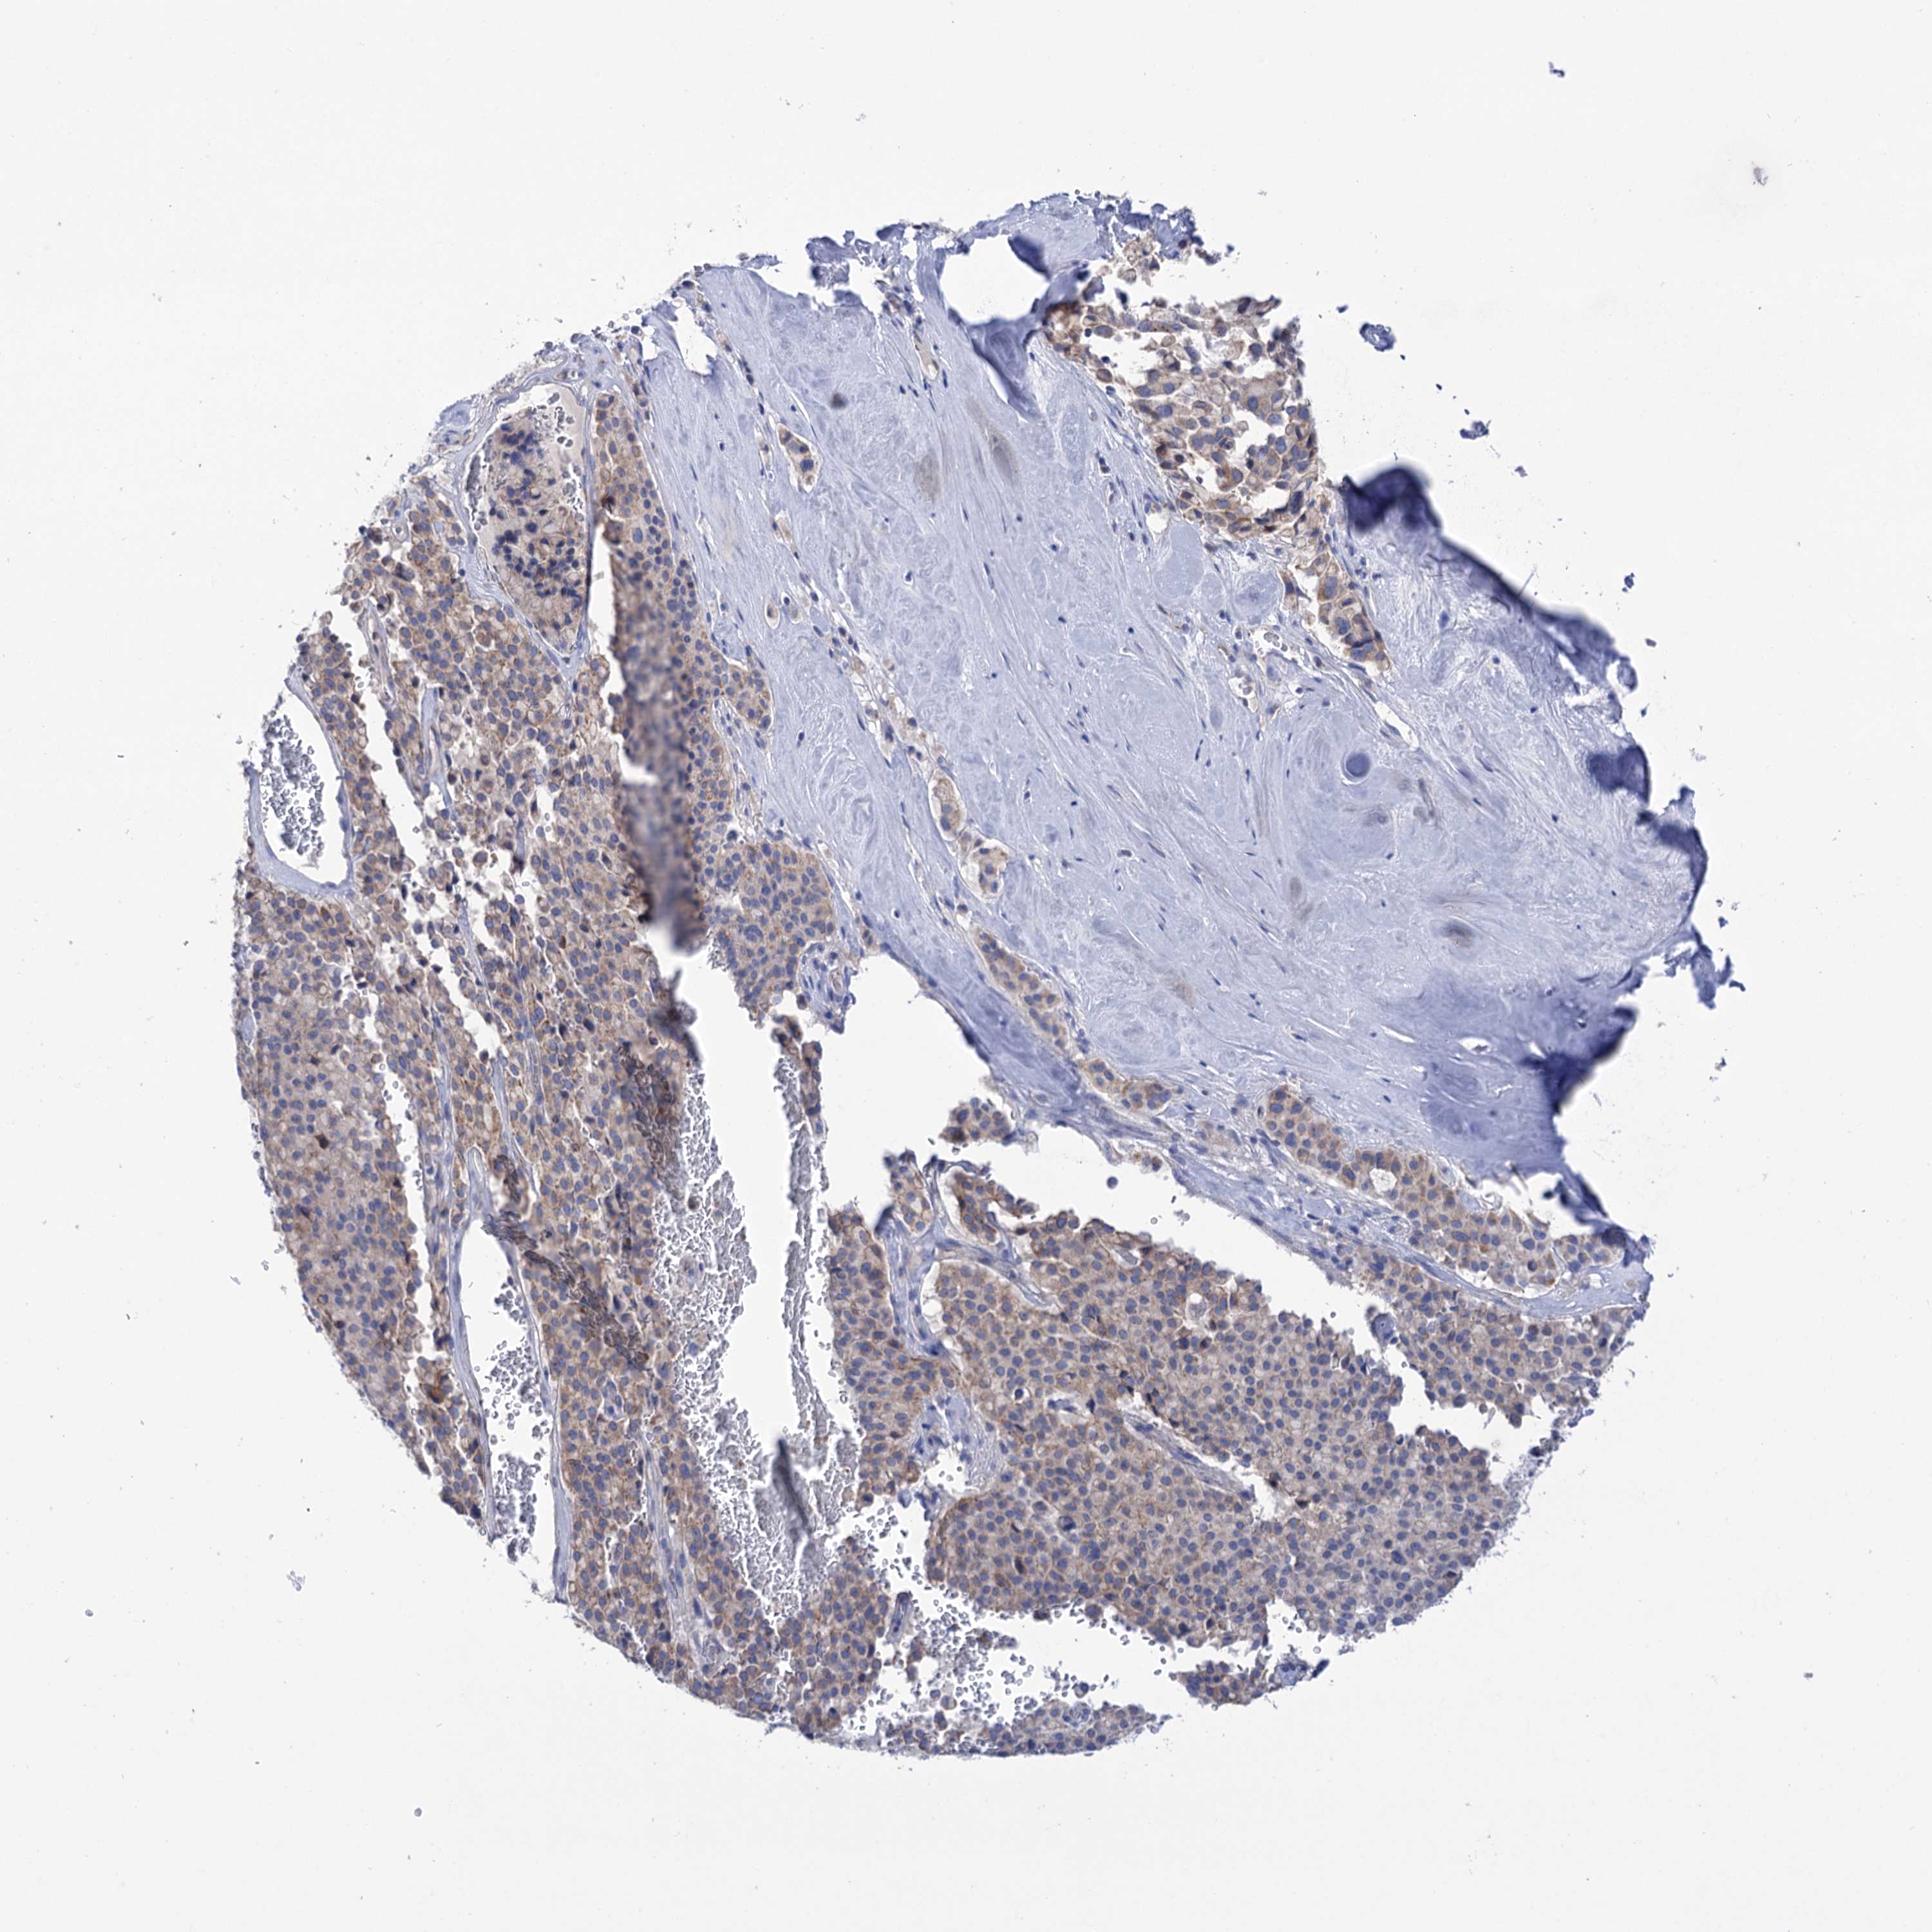

PANCREATIC CANCER - Protein expressioni

A mouse-over function shows sample information and annotation data. Click on an image to view it in a full screen mode. Samples can be filtered based on level of antibody staining by selecting one or several of the following categories: high, medium, low and not detected. The assay and annotation is described here.

Note that samples used for immunohistochemistry by the Human Protein Atlas do not correspond to samples in the TCGA dataset.

Antibody stainingi

Antibody staining in the annotated cell types in the current human tissue is reported as not detected, low, medium, or high, based on conventional immunohistochemistry profiling in selected tissues. This score is based on the combination of the staining intensity and fraction of stained cells.

Each image is clickable and will lead to virtual microscopy that enables deeper exploration of all samples and also displays staining intensity scores, fraction scores and subcellular localization as well as patient and tissue information for each sample.

Antibody HPA038721

Antibody HPA057610

Staining

High

Medium

Low

Not detected

Intensity

Strong

Moderate

Weak

Negative

Quantity

>75%

75%-25%

<25%

None

Location

Nuclear

Cytoplasmic/membranous

Cytoplasmic/membranous,nuclear

Adenocarcinoma, NOS